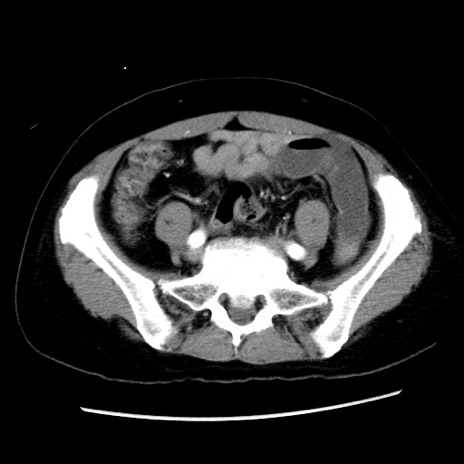

症例10(横断像)

【症例】 50歳代女性

【主訴】 腹痛

【現病歴】前日生レバーを食べた。今朝に排便あり。 昼前に突然発症の腹痛を生じ、当院救急外来を受診した。

【既往歴】 子宮筋腫にてで子宮全摘後

【身体所見】 意識清明、腹部:平坦、軟、下腹部やや左を中心に圧痛・反跳痛あり、筋性防御あり

【データ】WBC 7800、CRP 0.07